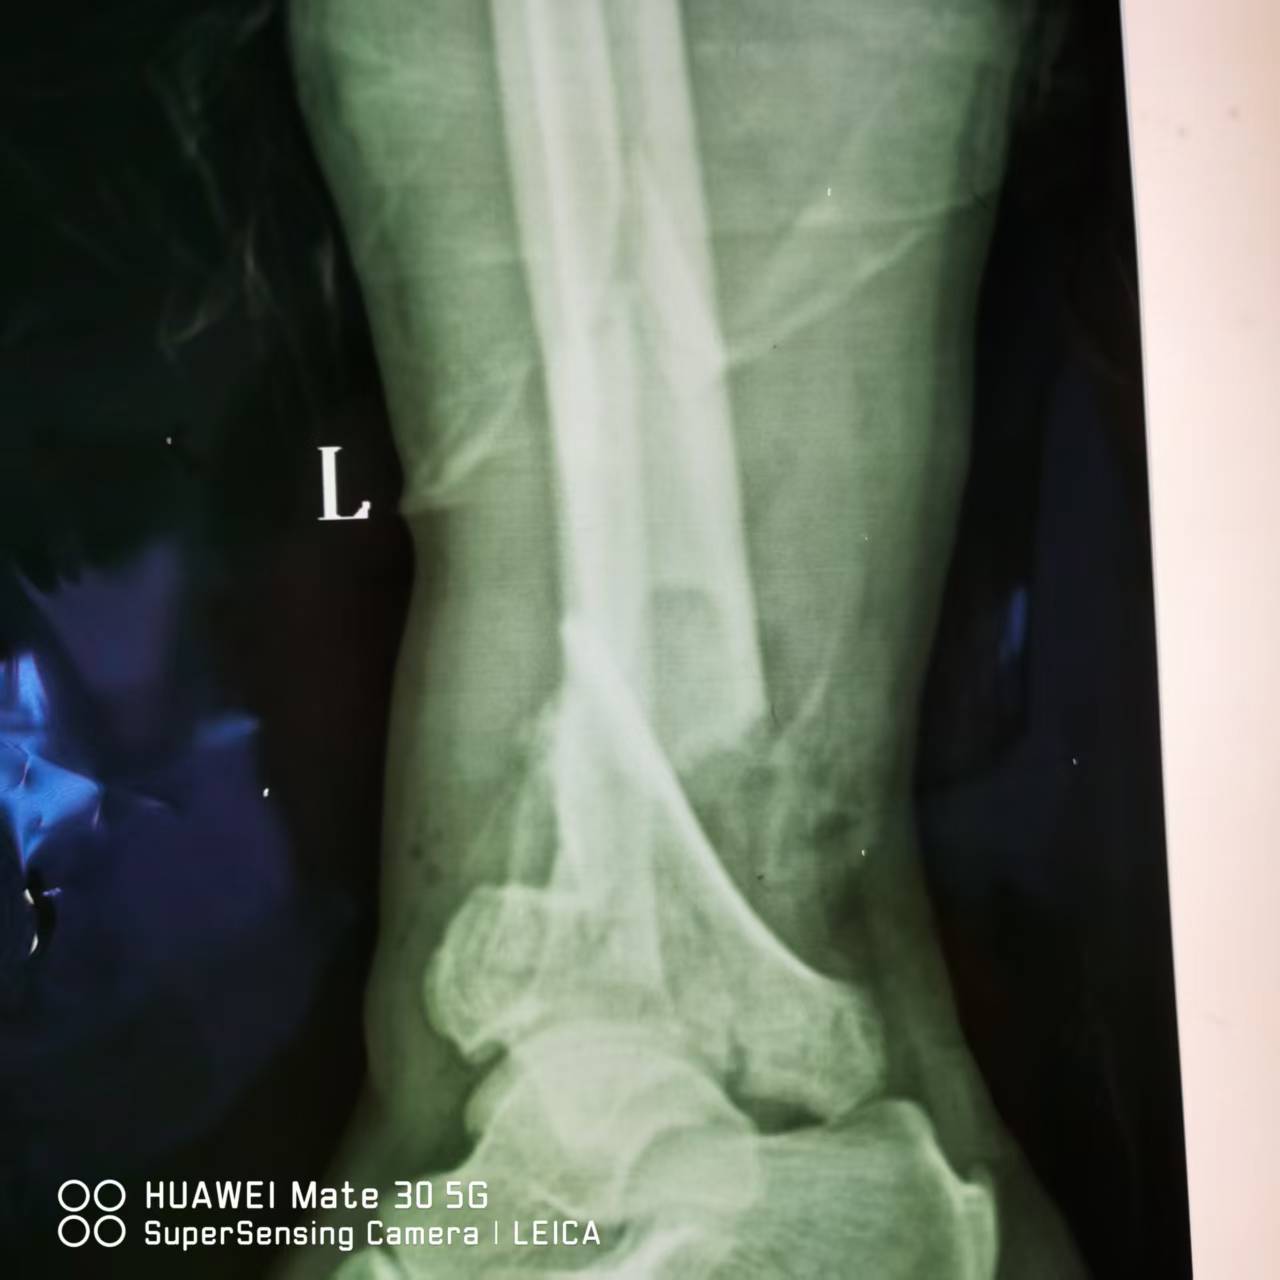

近日,阳光医院骨科成功为一名严重踝部摔伤患者分期实施手术。通过分阶段治疗策略有效解决复杂伤情,为患者康复奠定坚实基础。 患者赵XX在给房子换石棉瓦不慎摔下来,当时左小腿疼痛并流血,不能活动,伤口内骨折端外露,家人紧急将他送至阳光医院救治。 01 左踝关节骨折(Pilon骨折,AO分型C3) 经急诊摄片检查示:患者左胫骨远端粉碎性骨折,左腓骨中下段骨折(Pilon骨折,AO分型C3),同时伴有大面积皮肤软组织坏死及血管神经损伤,若直接进行骨折复位固定,感染风险极高且不利于伤口愈合。因骨折情况复杂,手术难度较大,我院骨科团队迅速组织多学科会诊,结合患者伤情特点,制定“清创维稳-骨折复位固定”的分期手术方案。 02 分期手术 第一阶段(急诊期),骨科团队优先对创面进行彻底清创,清除坏死组织并妥善处理血管神经损伤,鉴于开放性骨折创面污染重、感染风险高,同期行左胫腓骨骨折复位外固定架固定手术。术后予积极抗感染、对症治疗及精心护理,在医疗团队及家人支持配合下,伤口愈合良好。 第二阶段(二期手术内固定,一期术后2周),待软组织条件稳定后,骨科团队为患者行切开复位L型锁定钛板内固定术,术中同期取同侧髂骨行自体骨移植,术前术后均行影像学检查学评估。两次手术方案合理,衔接紧密,团队配合良好,术中实现骨折部位精准复位与可靠固定,治疗顺利完成。 术 后 目前,患者伤口愈合良好,骨折部位稳定性显著提升,已进入系统康复训练阶段。骨科主任董庆武表示:“分期手术策略可最大程度降低严重创伤的并发症风险,保障手术安全性与治疗效果。此次成功治疗展现了我院在复杂创伤救治领域的综合实力,也为同类病例提供了宝贵经验。”